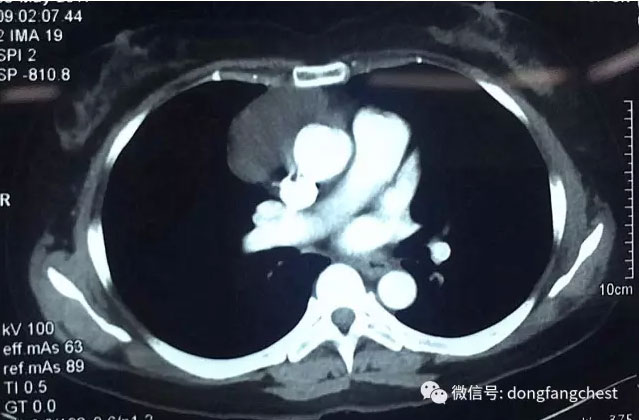

经多家医院就诊咨询后,张女士选择入住东方总院胸外科进行治疗。经过术前详细的检查和针对张女士“糖尿病、高血压病”的调整准备后,以朱胜、王鸿主任为首的胸心外科团队为张女士安排了“单孔胸腔镜纵隔肿物切除”手术。为最大程度减少患者的损伤以及切口的美观,主刀医师王鸿主任仅在2cm长的小切口下就成功完整切除了约6cm大小的纵隔肿瘤,手术过程仅耗时半个多小时,手术几乎没有出血。

据东方医院集团总院胸心外科王鸿主任介绍,张女士的纵隔肿瘤贴在纵隔大血管旁边生长,手术切除具有较大风险。传统手术治疗需要取15cm以上的大切口开胸切除肿瘤,手术创伤大,患者术后恢复慢。近10余年来,经过不断的探索、实践和发展,胸腔镜微创手术技术已经成为胸外科疾病的主要治疗手段。单孔胸腔镜手术技术是胸腔镜微创手术技术进一步发展的产物,目前已广泛应用于胸外科疾病的诊治:如胸外伤、气胸、胸膜及纵隔淋巴结的活检、肺局部切除、肺叶切除、肺段切除、纵隔肿瘤切除等。与传统胸腔镜手术技术相比,单孔胸腔镜手术切口设计取消了腋后线切口及腋中线观察孔切口,所有操作器械包括胸腔镜镜体均由一个3~5cm长的切口内进出,因此损伤更小,该切口选择部位为胸壁肌肉最薄弱的位置,术后疼痛更轻,对患者感觉和运动影响也更小。由于切口选择在相对隐匿的部位,如腋窝和乳房下缘,从而使得切口更加美观,也改善了手术对患者生理及心理上的影响。在应用过程中发现,对于心肺功能相对差的患者,单孔胸腔镜手术也可以降低手术的风险。